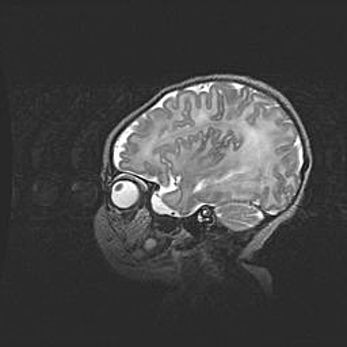

Мальформация Денди-Уокера. Киста задней черепной ямки.

Агенезия мозолистого тела.

Возраст: 2,5 месяца

Вес: 2420 г

Пол: женский

Окружность головы: 37 см

Срок гестации: 32 недели

Мальформация Денди—Уокера — редкий вид патологии ЦНС, представляющий собой врожденный порок развития каудального отдела ствола и червя мозжечка, ведущий к неполному раскрытию срединной (Мажанди) и латеральных (Лушка) апертур IV желудочка мозга. Для этогно синдрома характерна триада симптомов: гипотрофия червя мозжечка и/или полушарий мозжечка, кисты задней черепной ямки, гидроцефалия различной степени. В 70% случаев порок сочетается и с другими аномалиями головного мозга, в частности с агенезией мозолистого тела.